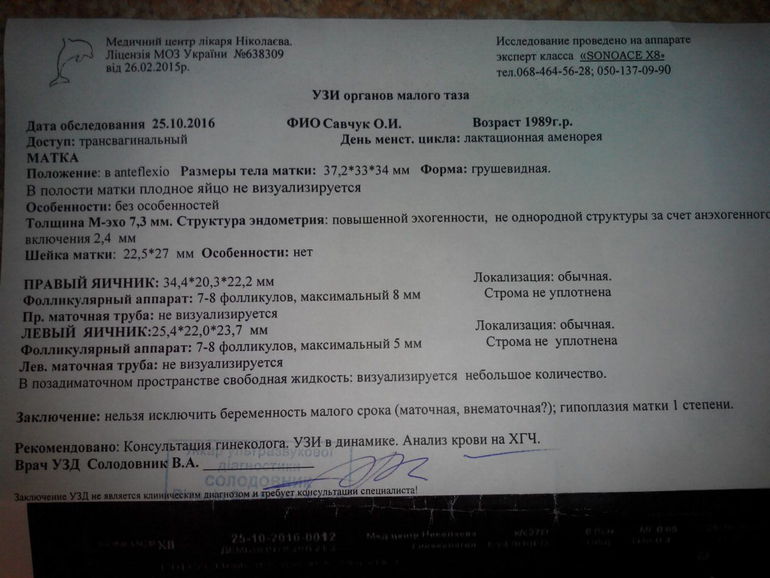

Была на УЗИ..

Я тоже 15.09 была на УЗИ,сильные боли в области шва после КС,и нарушения цыкла,он у меня с 3 месяцев ребёнкиных,на ГВ до сих пор,до 5 месяцев исключительно ГВ.Начинались вроде вовремя,но если положеных 5 дней,то потоп,а последние были в августе 10 дней,месяц пропущен,трубы перевязала после 3-го малыша,и всё равно делала тест,отрицательный,спайки от яичников к стенке матки,опущен правый яичник,вот такие спазмы меня берут.Это всё ГВ фокусы выдаёт у меня,но жидкости не было.Запаситесь терпением,тест ещё через неделю сделайте,на всякий случай.Боялась внематочной до дури,наревелась,навнушала себе до нервного тика.

И я боюсь внематочной. Сказали возможно беременность 2недели. И еще матка маленькая и опущена..